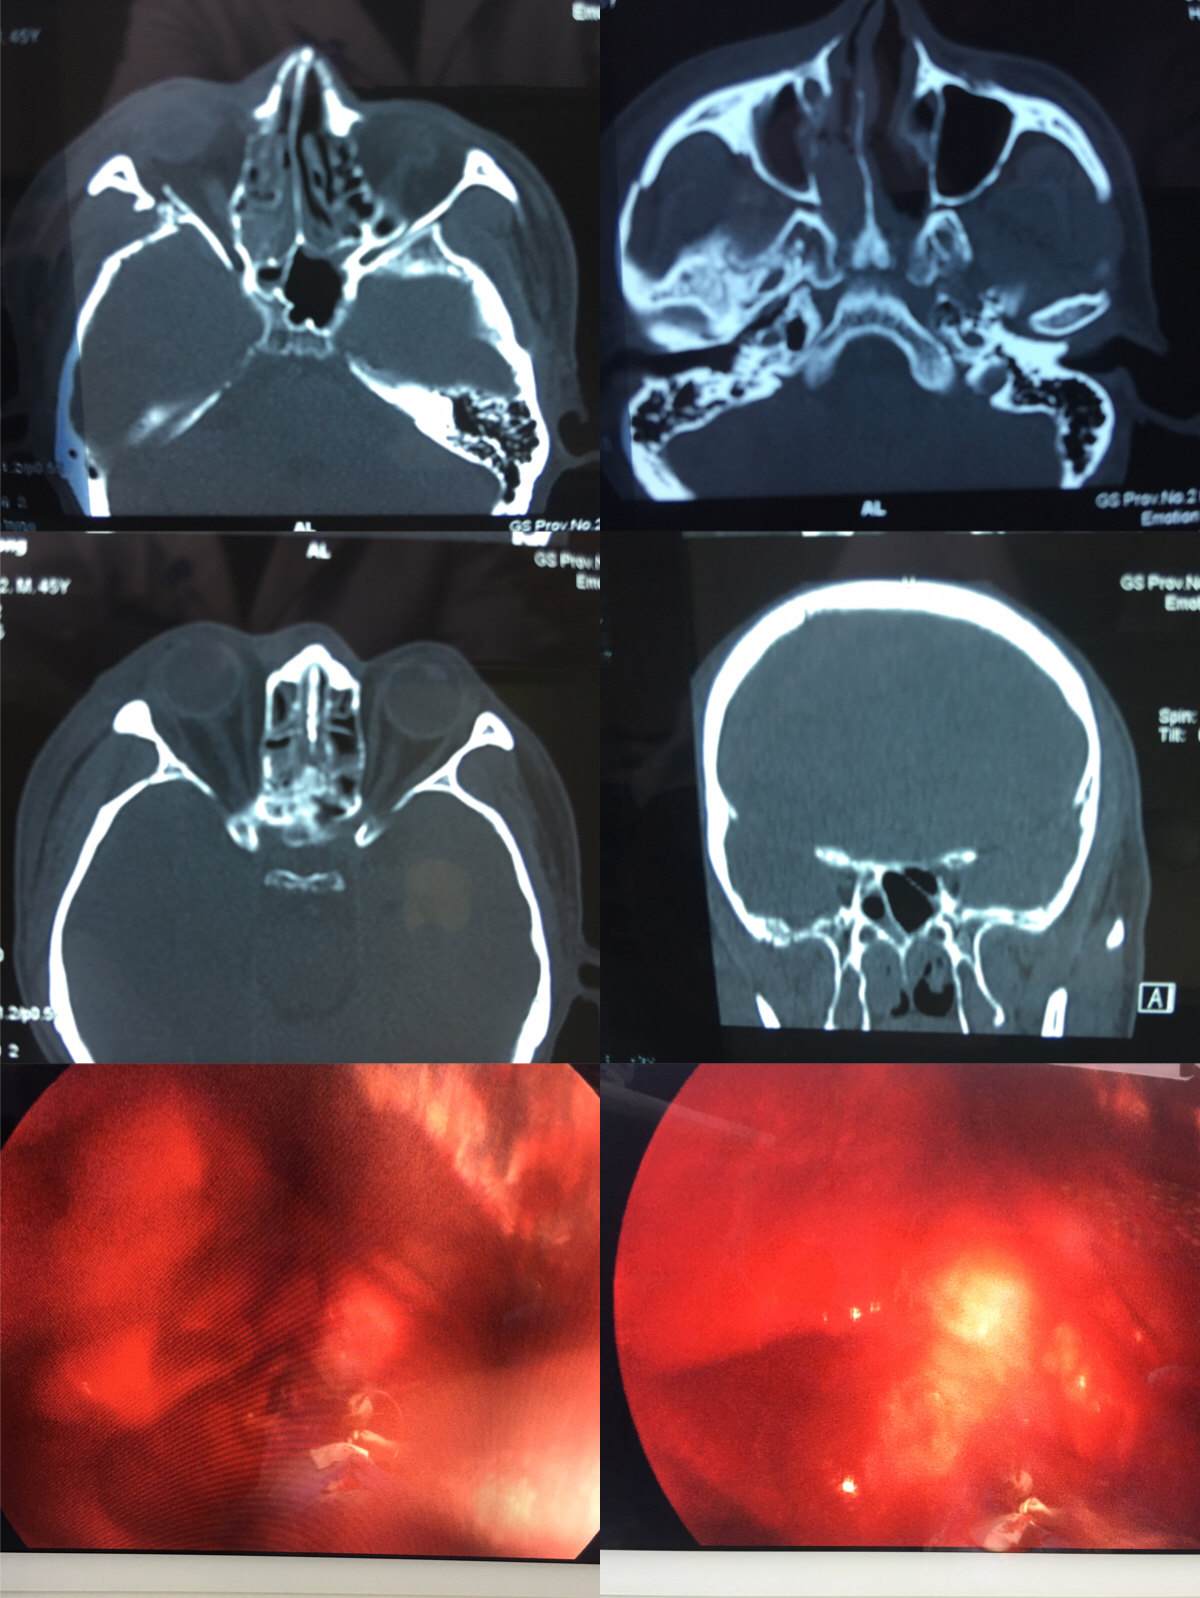

术前ct见右眼眶外侧壁骨折,视神经管受压

王拓教授团队:内镜视神经管减压手术分享